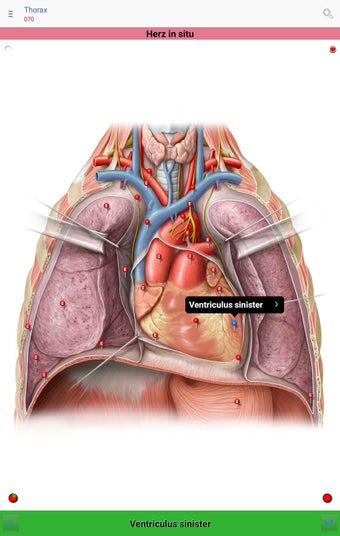

The app consists of different sections, each of which contains information about a specific part of the body. You will learn about the different organs, as well as the muscles, bones, and other important structures. You can test yourself with a unique quiz that consists of multiple-choice questions.